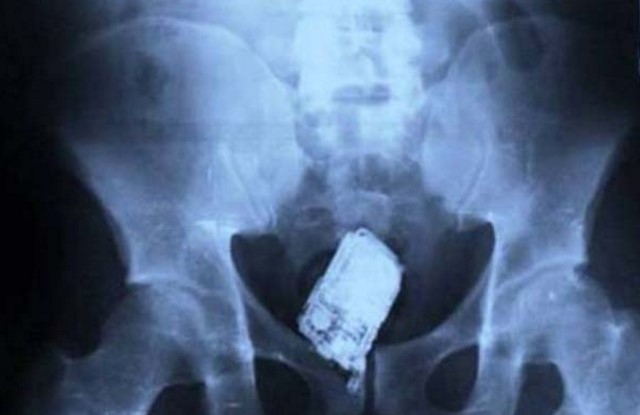

7. Ponsel.